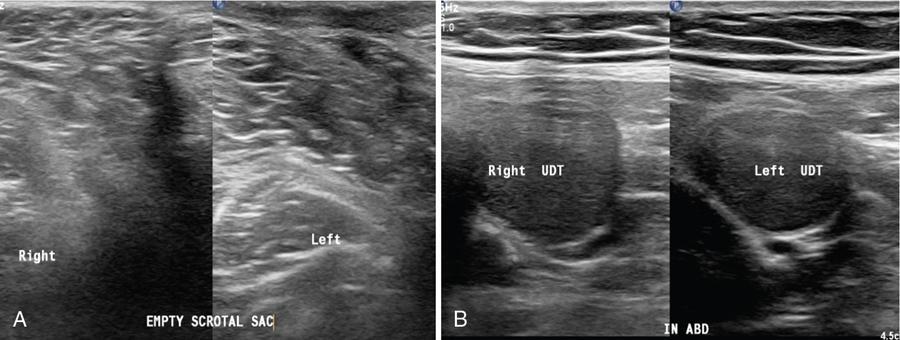

In male children, hydrocele is the most frequent cause of painless scrotal swelling. Its incidence is about 0.7%–4.7% in male infants and prevalence in adult men is estimated about 1%. Hydrocele is common in newborns and usually disappears without treatment by the age of 1 year. Older boys and adult men can develop hydrocele (acquired) due to infection, inflammation, torsion, trauma and tumour. One to two millilitres of serous fluid can be seen in tunica vaginalis cavity and should not be erroneously diagnosed as hydrocele (Fig. 11.8.9).

Fig. 11.8.9(A) Transverse US scans of both hemiscrotum showing echo free fluid collection around right testicle (hydrocele). (B and C) Depicting the US Panoramic and 3D images of hydrocele.

2. Imbalance of production and reabsorption of fluid within tunica vaginalis space in scrotal sac. This disturbance may be a result of infection, tumour, trauma, torsion, defective lymphatic drainage after surgery for varicoceles and inguinal hernias or idiopathic (Fig. 11.8.10).